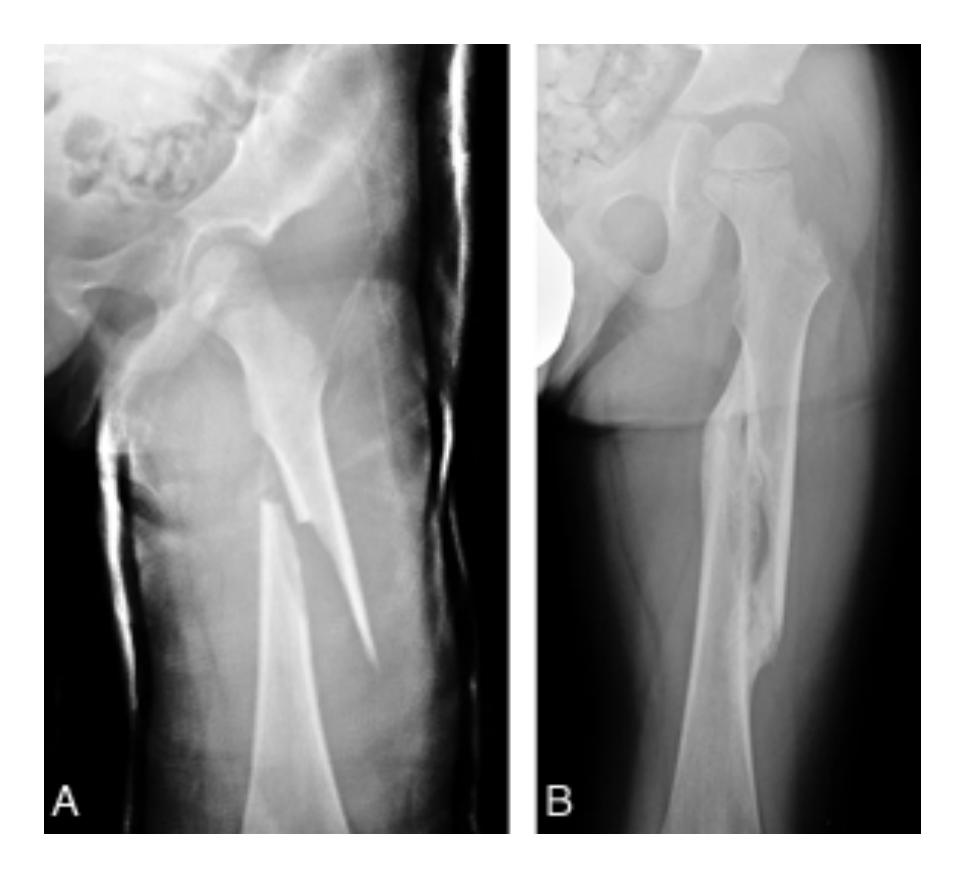

Femoral Fractures

Intertrochanteric Fracture

Diagnosis: Intertrochanteric fracture of neck of femur Treatment: Dynamic hip screw or proximal femoral nail

Femoral Shaft Fracture

Diagnosis: Femoral shaft fracture Management:

- IV line, fluids, blood transfusion

- 2 views and 2 joints x-rays (must see hip joint)

- Treatment of choice: Locked intramedullary nail